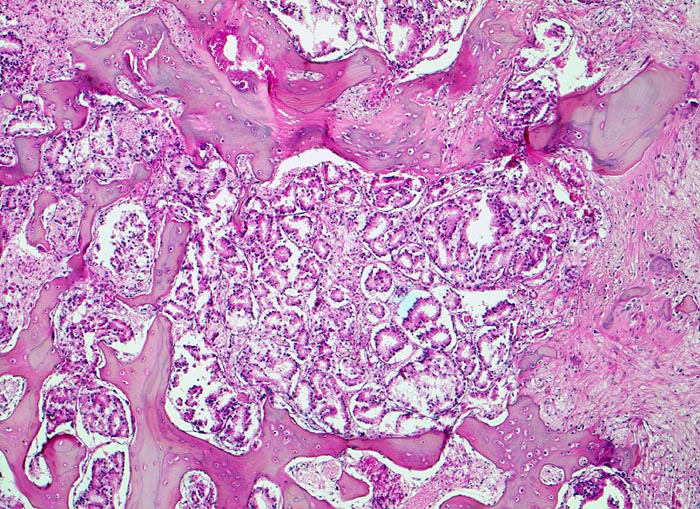

Morphologische Merkmale:

• Fehlen von blutbildendem Knochenmark.

• Infiltration des Knochemarks durch kleine dichtgepackte, kribriforme Strukturen ausbildende Karzinomdrüsen.

• Osteplastische Metastase: Faserknochenneubildung zwischen vorbestehenden Trabekeln.

• Anhand der Histologie kann lediglich die Diagnose einer Metastase eines Adenokarzinoms gestellt werden. Kleine, solide Verbände bildende Tumordrüsen und grosse Nukleolen sind typisch für ein Prostatakarzinom. Die Diagnose muss aber durch den Vergleich mit der Morphologie des Primärtumors oder eine Immunhistochemische Untersuchung (PSA, PSAP) bestätigt werden.